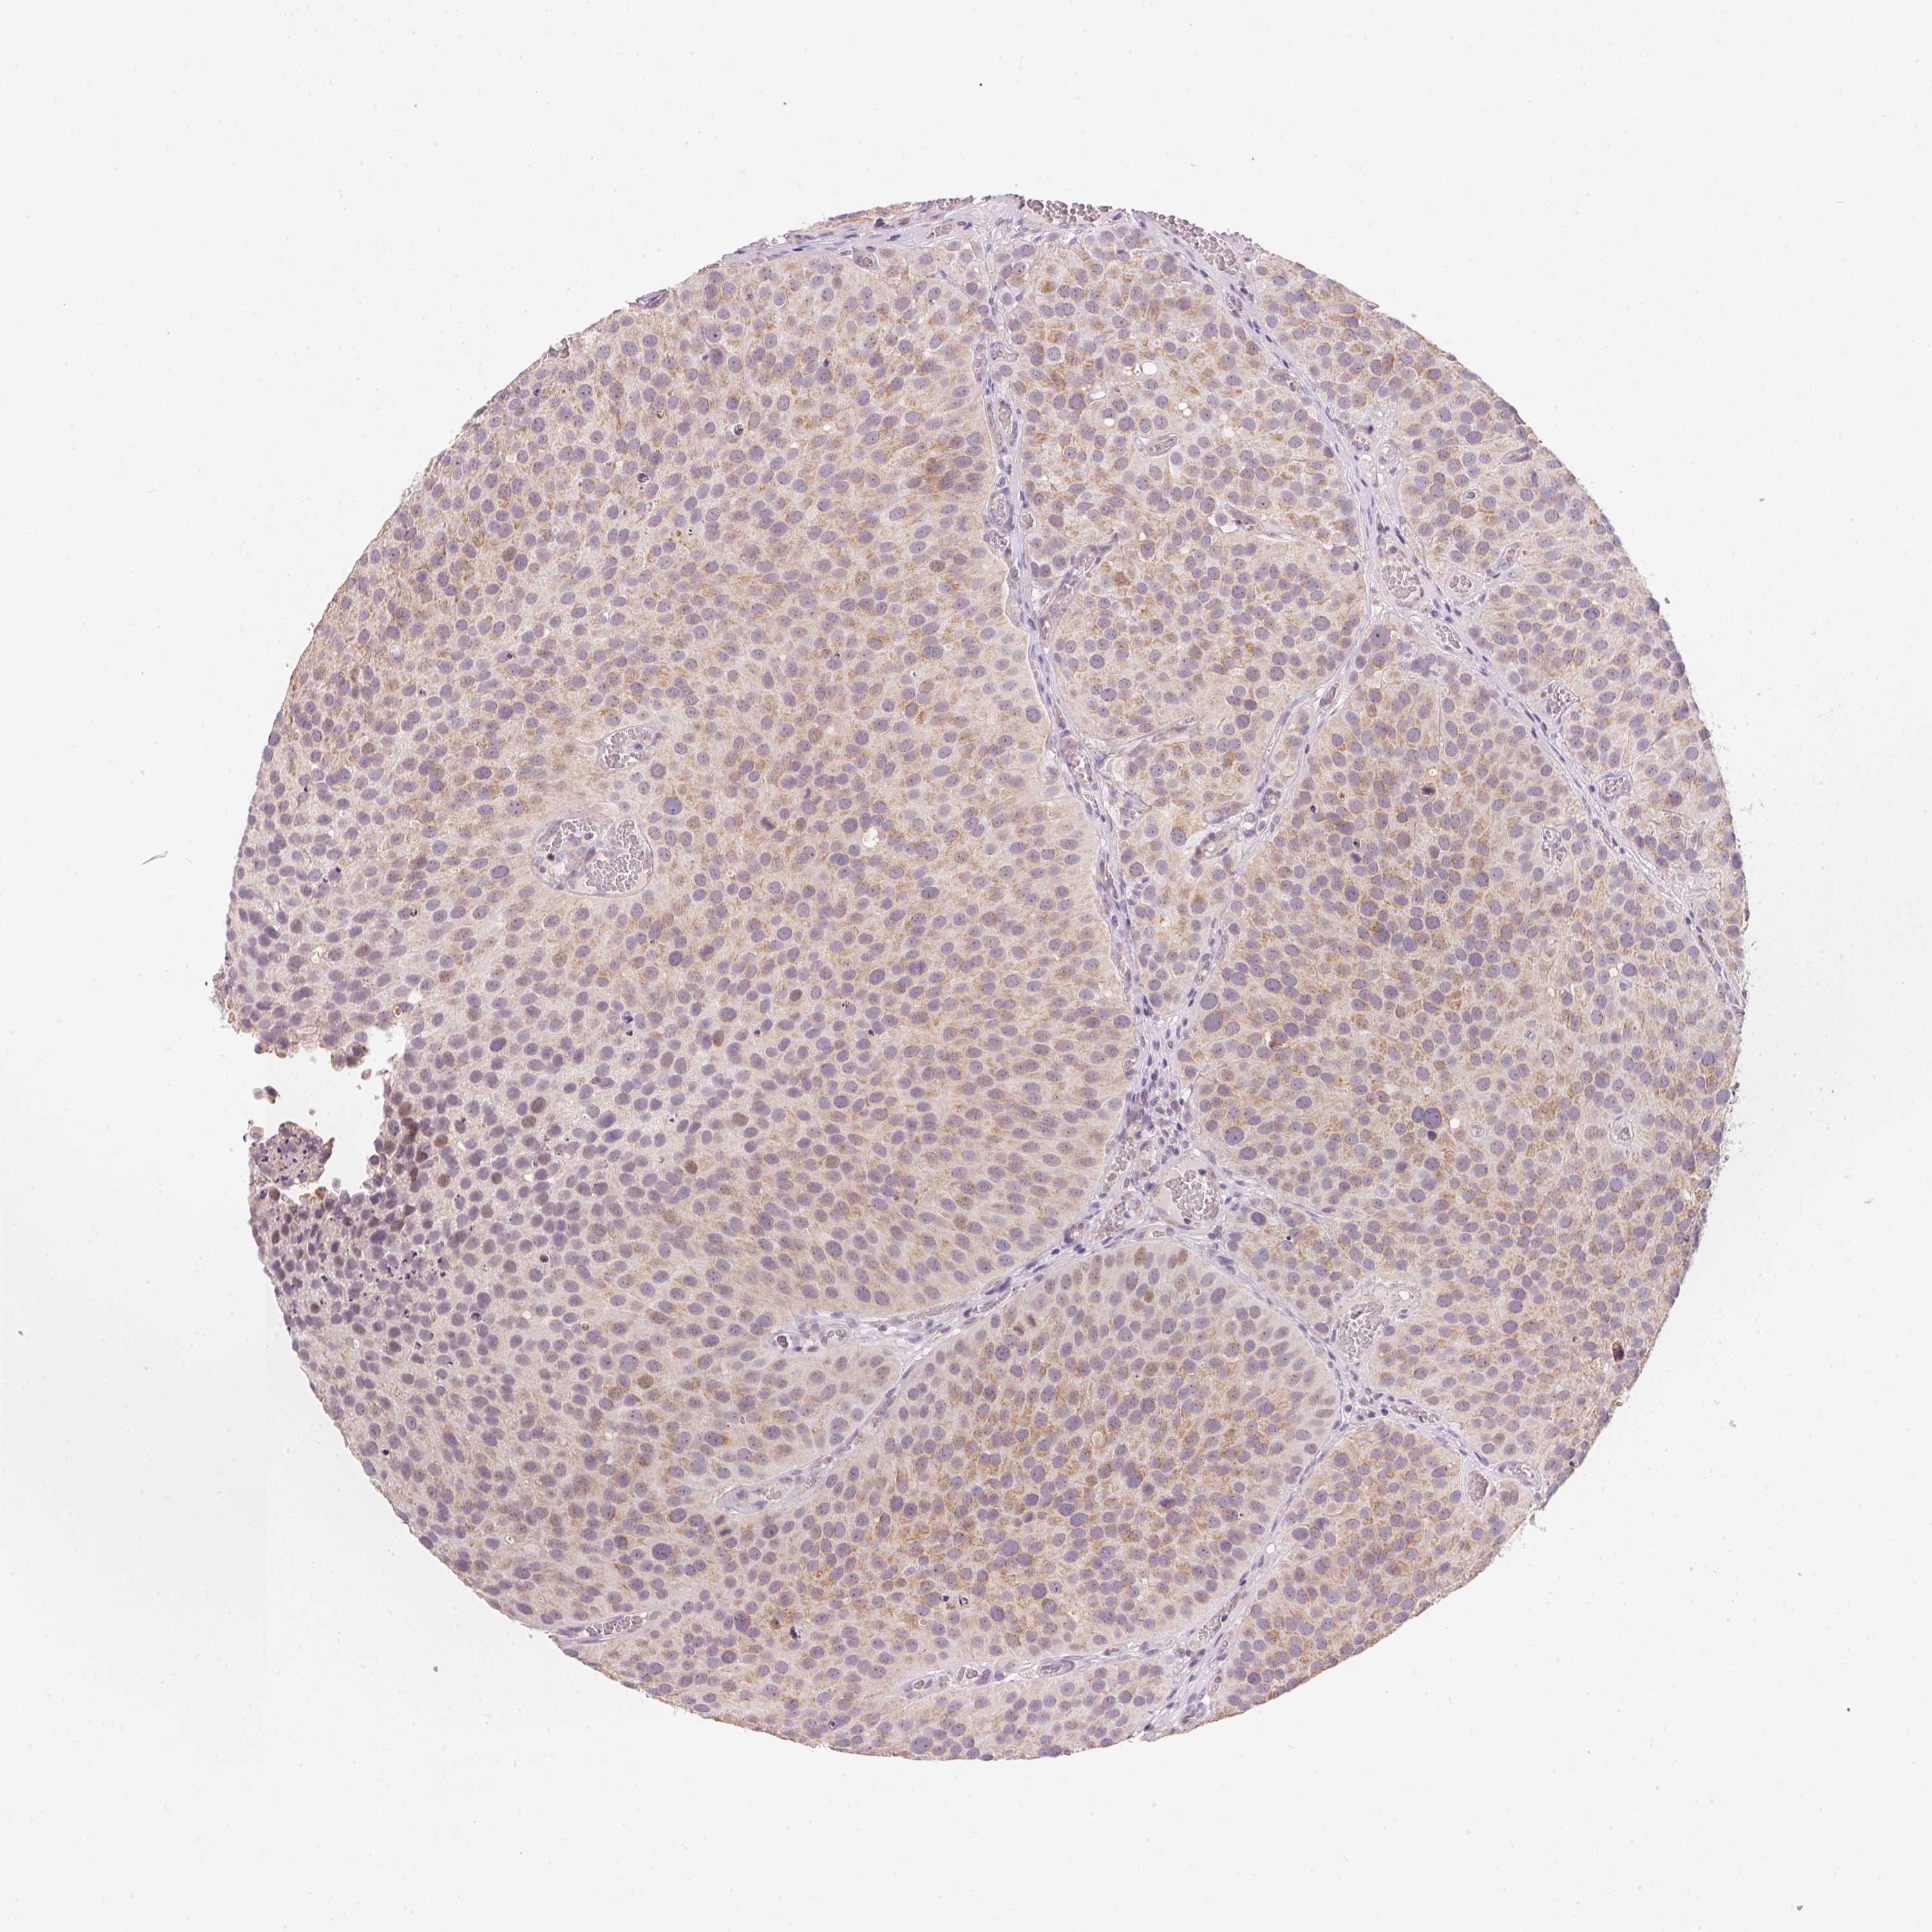

UROTHELIAL CANCER - Protein expressioni

A mouse-over function shows sample information and annotation data. Click on an image to view it in a full screen mode. Samples can be filtered based on level of antibody staining by selecting one or several of the following categories: high, medium, low and not detected. The assay and annotation is described here.

Antibody stainingi

Antibody staining in the annotated cell types in the current human tissue is reported as not detected, low, medium, or high, based on conventional immunohistochemistry profiling in selected tissues. This score is based on the combination of the staining intensity and fraction of stained cells.

Each image is clickable and will lead to virtual microscopy that enables deeper exploration of all samples and also displays staining intensity scores, fraction scores and subcellular localization as well as patient and tissue information for each sample.

Antibody HPA067252

Staining

High

Medium

Low

Not detected

Intensity

Strong

Moderate

Weak

Negative

Quantity

>75%

75%-25%

<25%

None

Location

Nuclear

Cytoplasmic/membranous

Cytoplasmic/membranous,nuclear

Urothelial carcinoma, High grade

Urothelial carcinoma, NOS

Urothelial carcinoma, Low grade